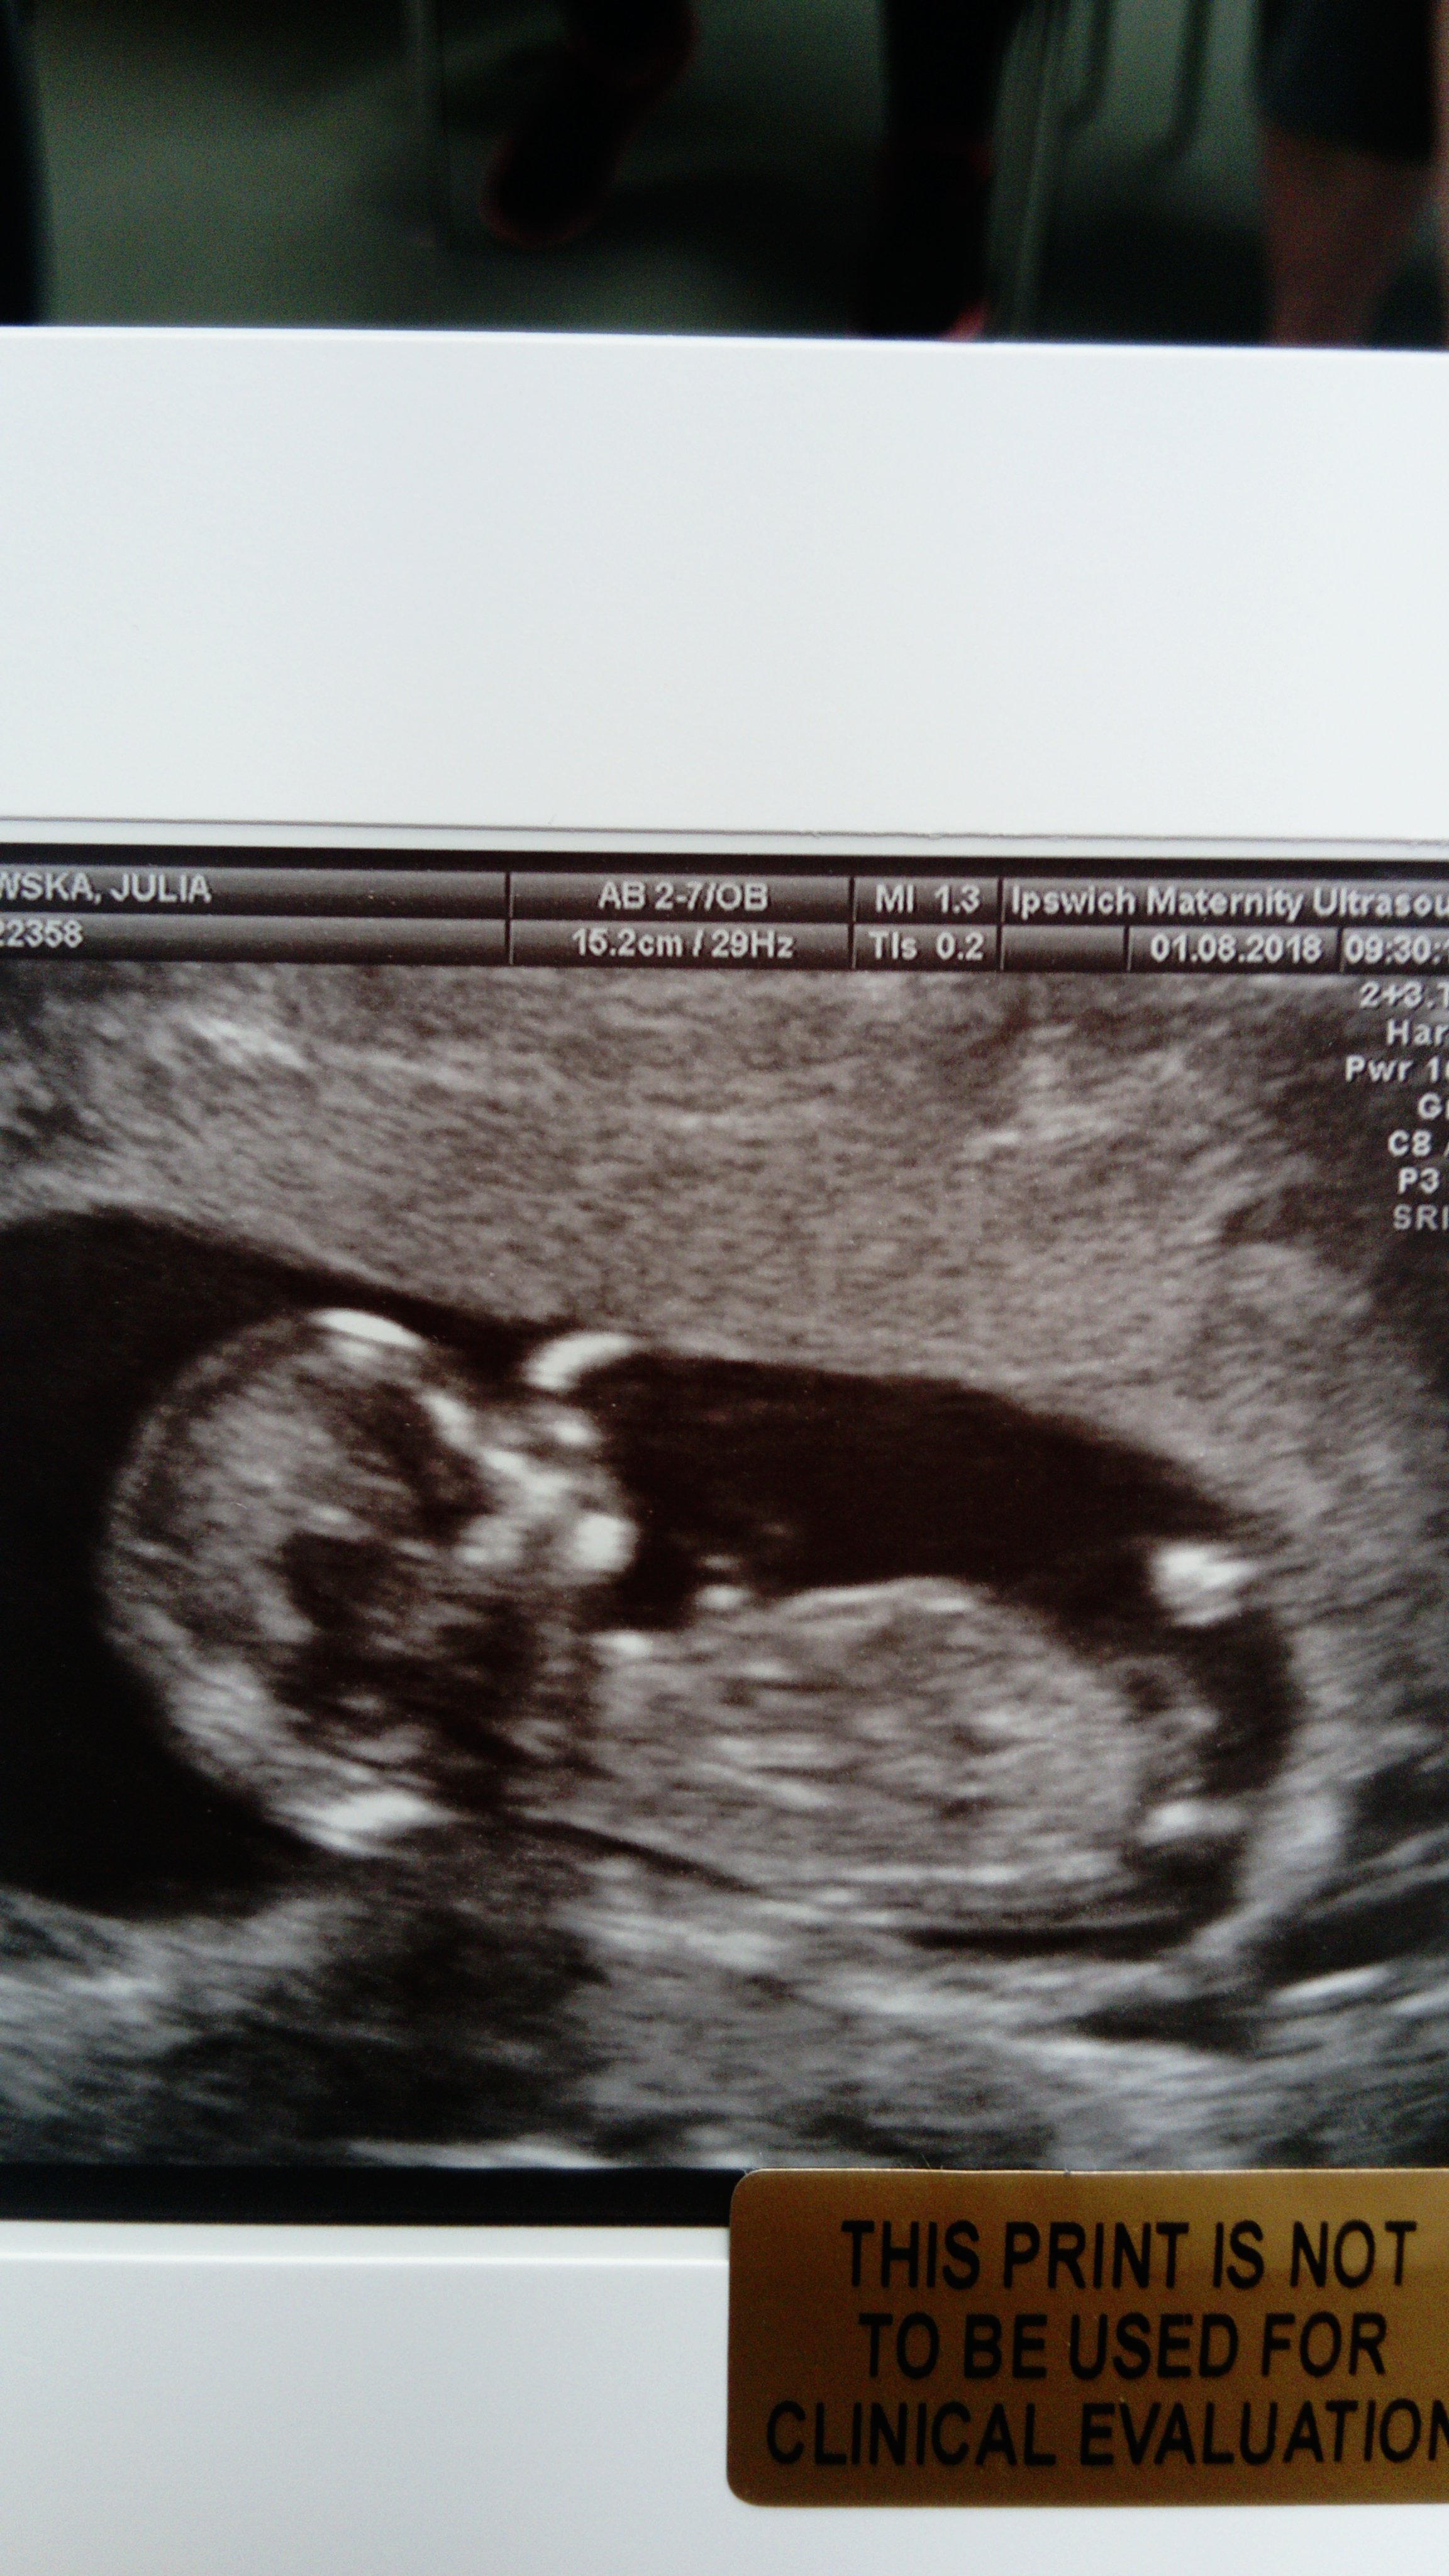

Już po wizycie :) wszystko w porządku. Dzidzia wygląda na zdrowa. Ma 5,85 cm, serduszko biło 160/min, NT mamy 0,7 mm :) termin porodu pozostaje na 14.02 :) pierwszy typ płci to wg lekarki dziewczynka, a mówi, że się jej rzadko zdarza pomylić ;) także mogą być 2 dziewczyny :D a tak wygląda mały alien :D

IMG_20180801_100737.jpg

• IMG_20180801_100737.jpg